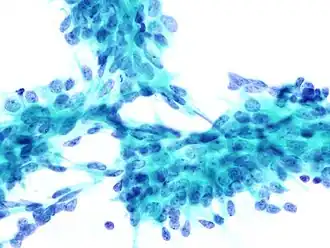

La biopsie à l’aiguille fine (BAF) ou cytoponction, est une méthode de diagnostic consistant à prélever des cellules et du tissu dans des nodules ou du liquide dans des kystes et des ganglions lymphatiques à l'aide d'une aiguille très fine montée sur une seringue pour effectuer ensuite un examen cytologique du prélèvement au microscope. C'est une procédure chirurgicale de diagnostic sûre et non invasive, qui évite souvent les biopsies chirurgicales majeures. Contrairement à la biopsie par forage, la biopsie à l'aiguille fine est généralement indolore et ne provoque que peu de complications (saignement, infection). Elle est le plus souvent employée pour la détection des cancers du sein, de la thyroïde ou des ganglions lymphatiques dans le cou, l'aine ou l'aisselle[1].